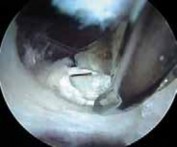

TECHNIQUES A B C D E F G H I ### FIG 4 • A–G. The iliopsoas tendon of the right hip is exposed from the peripheral compartment. A. The initial tendon viewed through a capsular window is fully identified, but is abnormally small. B. This tendon is released with a basket. C. A stump remains. D. This is resected with a shaver. E. Further dissection exposes a more substantial portion of the iliopsoas tendon. F. This is released as well. G. Complete release of the bifid tendon is documented. H,I. Viewing the iliopsoas tendon of a right hip at its insertion on the lesser trochanter within the iliopsoas bursa. H. A bifid iliopsoas tendon is identified with medial (

) and lateral () bands separated by a vessel (

two white asterisks

) coursing perpendicular. I. The lateral band (

black asterisks

) has been released with a flexible RF device, revealing the medial band (

white asterisk

) which subsequently is released. (Courtesy of J. W. Thomas Byrd, MD.)**